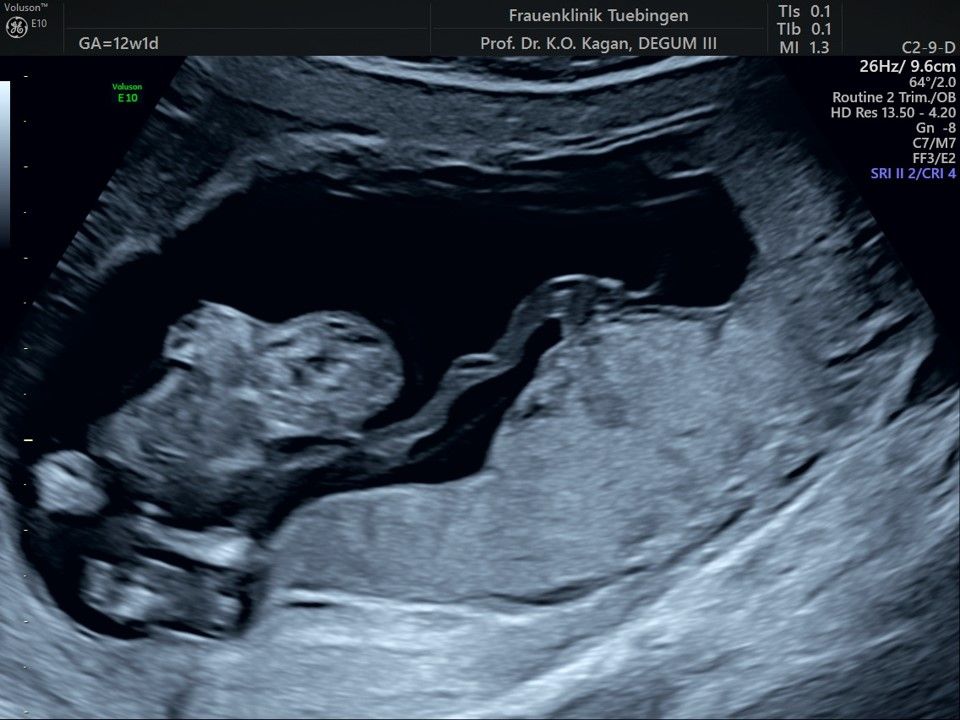

Im Rahmen des Ersttrimester-Screenings untersuchen wir die Organe des Feten mittels Ultraschall. Dabei machen wir auch gerne ein Bild für Sie.

Obwohl der Fet zu diesem Zeitpunkt erst zwischen 5 und 8cm groß ist, lassen sich bereits etwa die Hälfte aller schwerwiegenden Fehlbildungen erkennen bzw. ausschließen. Sollten wir eine Auffälligkeit sehen, werden wir mit Ihnen den Befund und das weitere Vorgehen ausführlich besprechen.

Die eigentliche Organuntersuchung findet um die 20.SSW (zweites Screening) statt. Das Ersttrimester-Screening und das zweite Screening sind sich ergänzende Untersuchungen und ersetzen sich gegenseitig nicht.